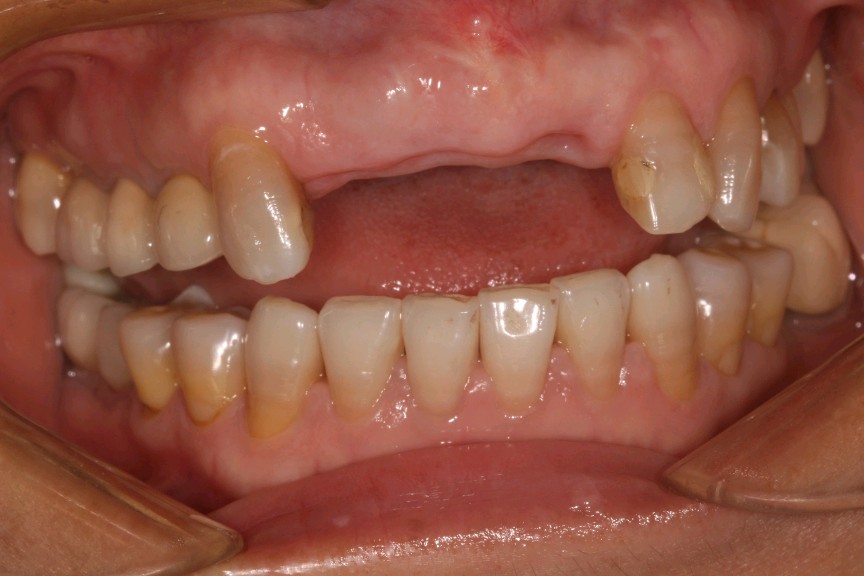

患者女,四十岁,前牙松动一个月。口内检查:12,11,21连冠修复,松动(+++),12冠根折。X线显示:骨密度良好,牙槽骨骨量不足。治疗计划:拔除+植人骨粉骨膜+种植修复。

术前